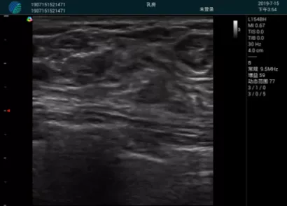

M20查看:囊內(nèi)回聲均勻,邊界清晰,囊壁光滑

M20引導(dǎo)抽吸術(shù)后囊腫消失,原區(qū)域空腔形成,脂肪層與腺體層架構(gòu)發(fā)生改變

超聲以操作簡單、定位準(zhǔn)確、實(shí)時(shí)顯像、費(fèi)用低廉等優(yōu)勢(shì),而成為麥默通乳腺活檢治療乳腺腫塊最常見的引導(dǎo)手段,已逐步在各大醫(yī)院開展此類手術(shù)。

2、超聲的可視化操作,能準(zhǔn)確的顯示病灶的位置、最大徑,選擇合適的刀具,決定切口的位置和方向,避開血管、減少出血危險(xiǎn)并實(shí)時(shí)觀察乳腺病灶的切割情況,避免造成腫塊組織殘留